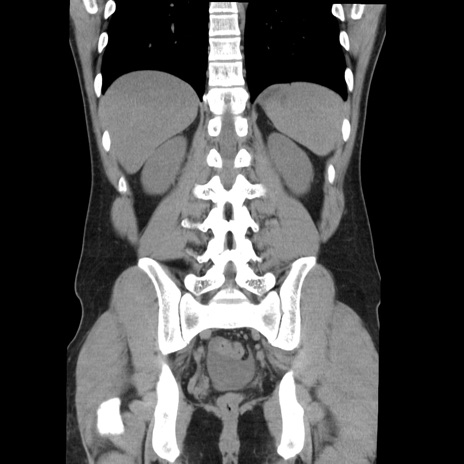

症例36(冠状断像)

【症例】20歳代 男性

【主訴】心窩部痛

【現病歴】今朝より上腹部痛あり。一旦軽快していたが再度出現したため救急要請。昨日夕に白身の魚を含む刺身を食べた。

【身体所見】BP 136/89mmHg、HR 74/min、BT 37.0℃、腹部:膨満、軟、心窩部に圧痛あり。反跳痛なし、筋性防御なし、腸雑音やや亢進あり。

【データ】WBC 17700、CRP 0.48